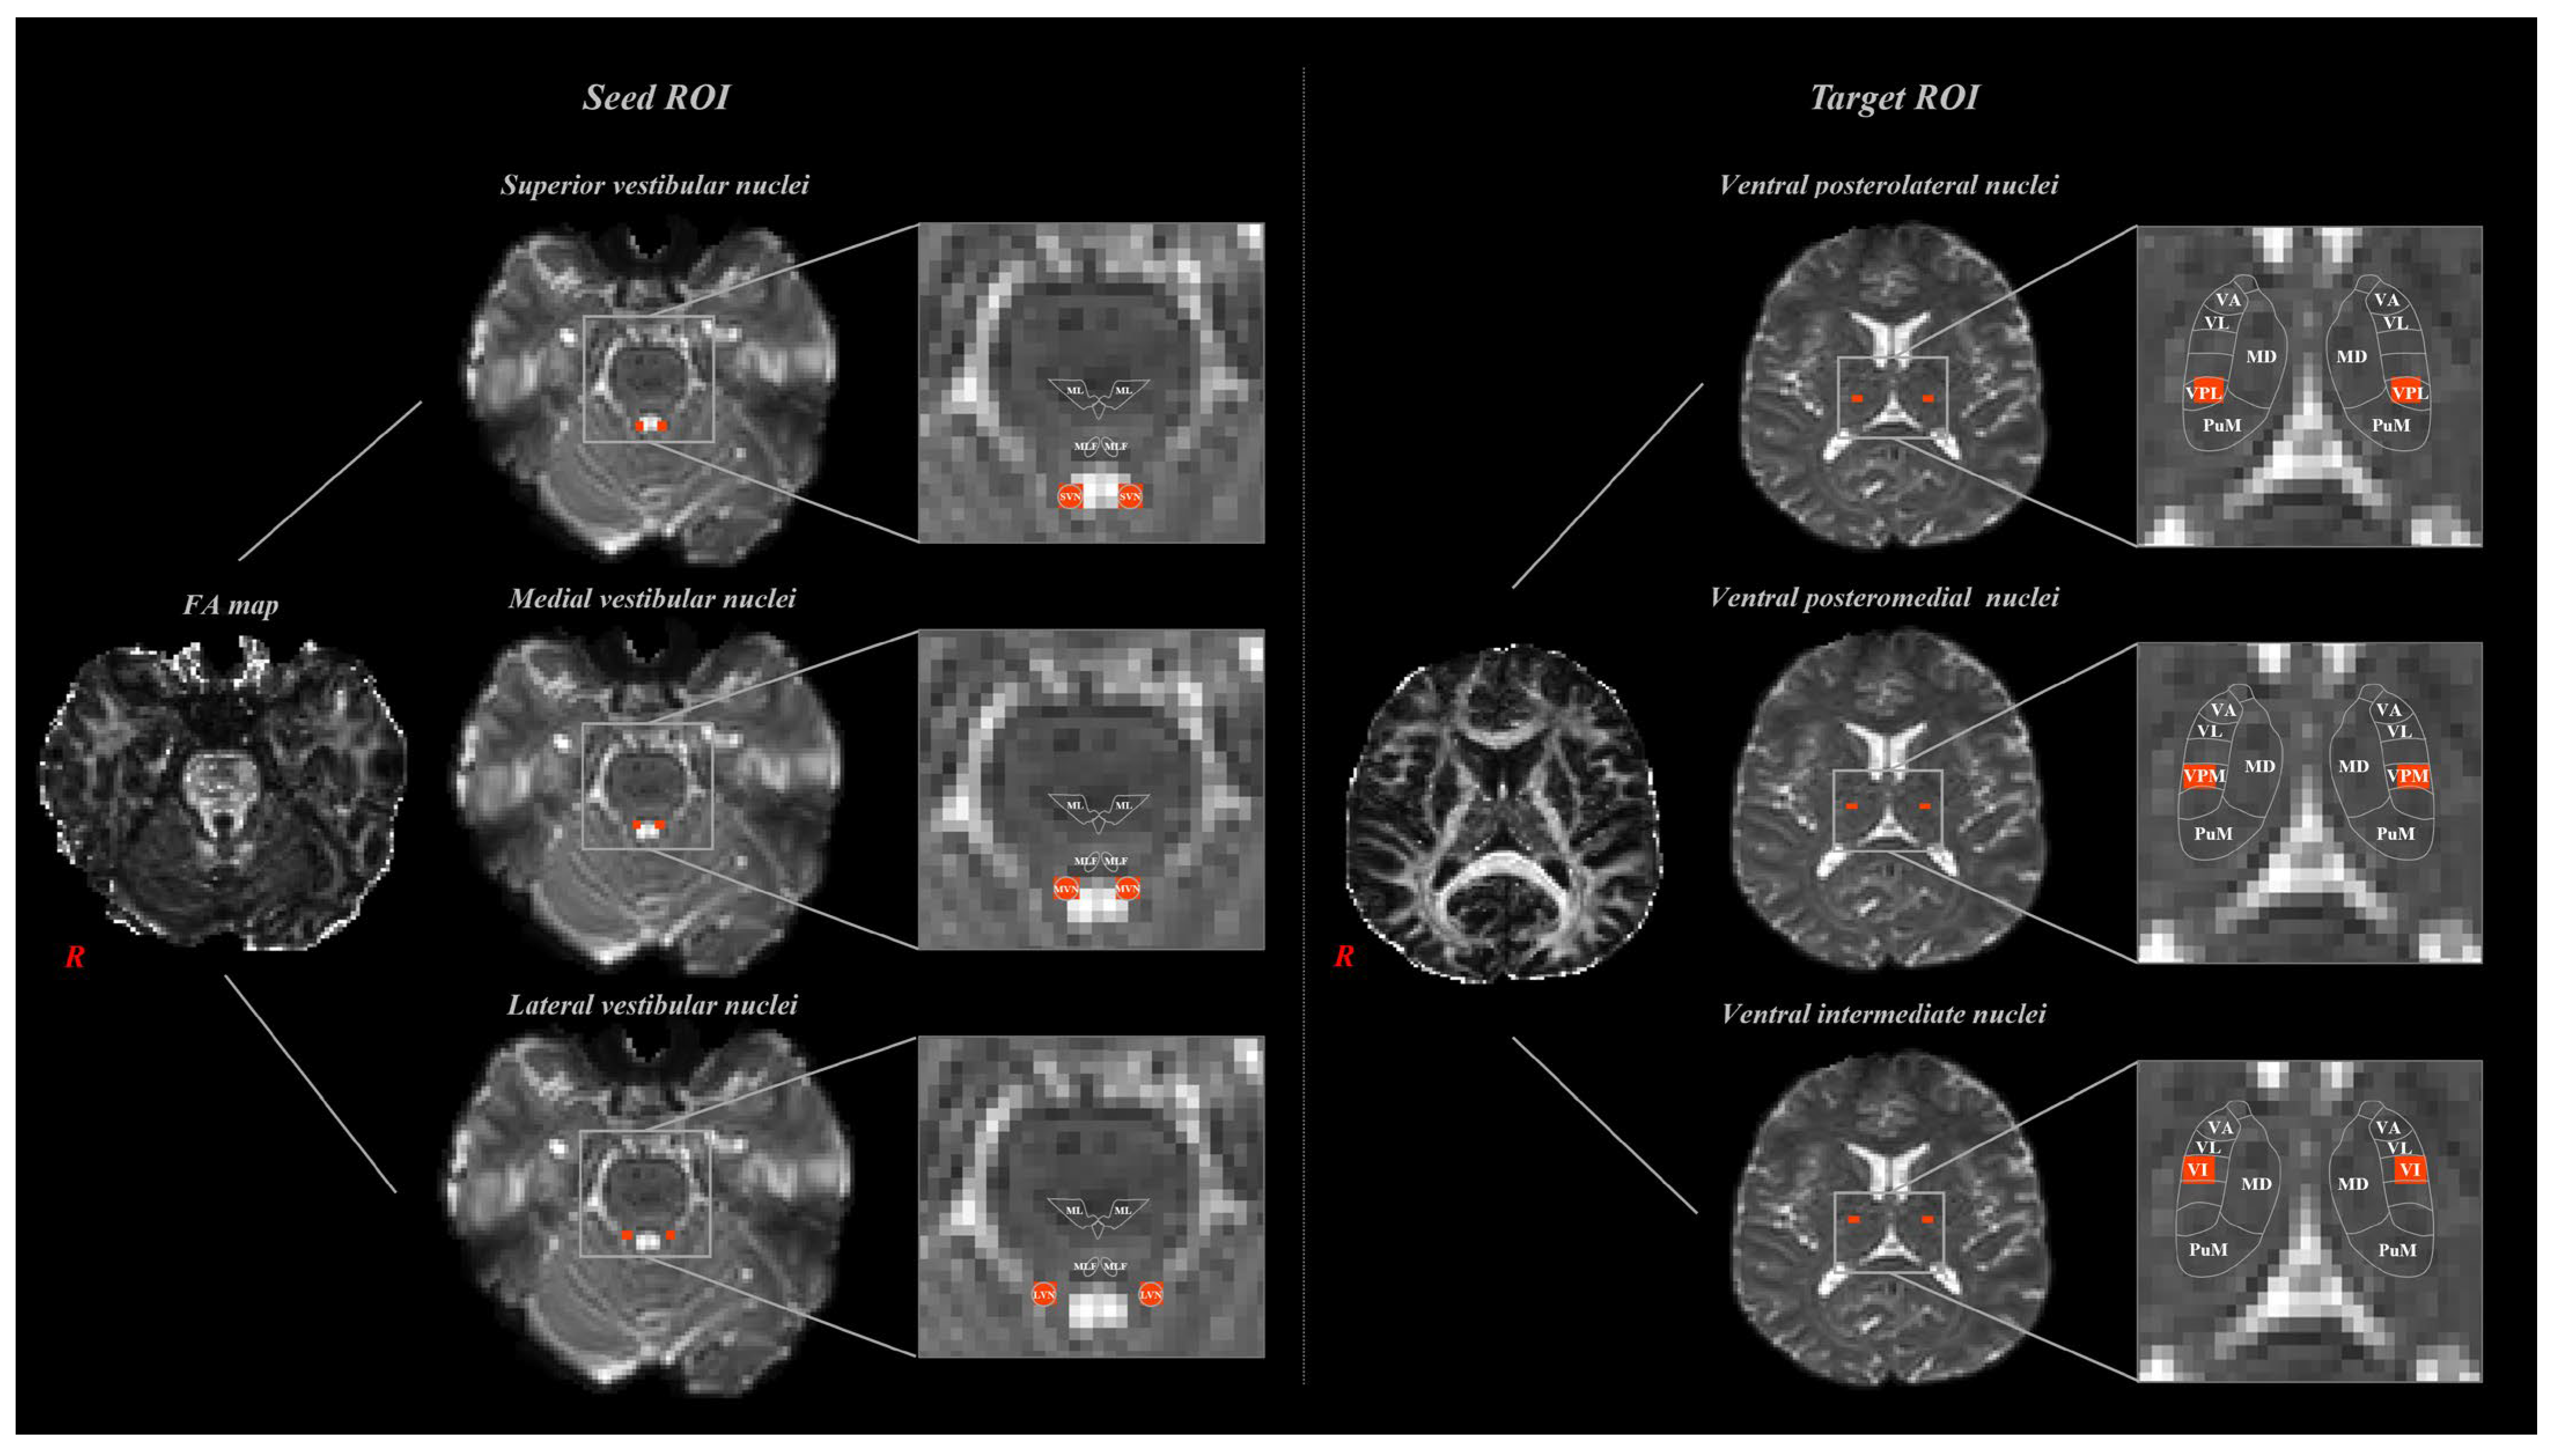

2.2. Diffusion Tensor Image Tractography

2.3. Fiber Tracking